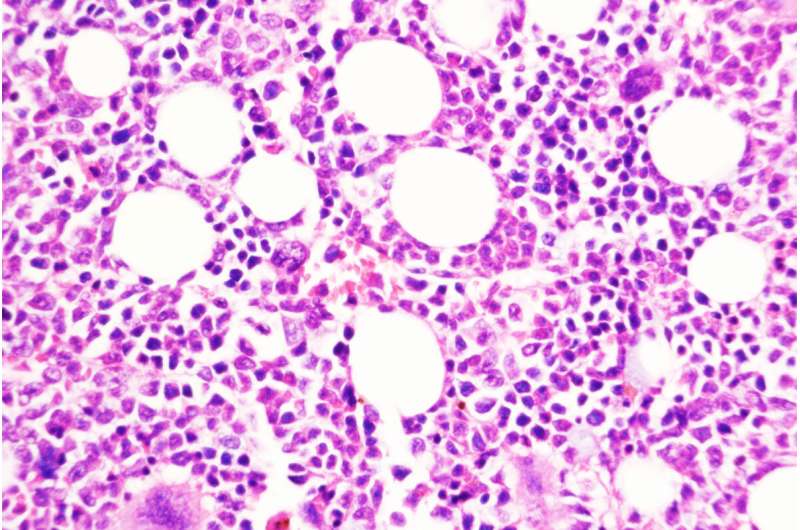

圣路易斯華盛頓大學醫學院的一項研究提出了一種預防慢性、生長緩慢的血癌發展為侵襲性白血病的策略。圖中顯示的是用一種化合物阻斷DUSP6的小鼠骨髓,DUSP6是由慢性疾病轉變為侵襲性疾病的關鍵分子。

使用遺傳技術刪除DUSP6基因可以防止這種癌癥模型小鼠向侵襲性疾病的轉變。研究人員還測試了一種抑制DUSP6的藥物化合物,并發現這種化合物(僅用于動物研究)在兩種不同的癌癥小鼠模型和從患者身上取樣的人類腫瘤小鼠中阻止了慢性疾病向侵襲性疾病的進展。在這些模型中,通過基因和藥物降低DUSP6水平也能減少炎癥。